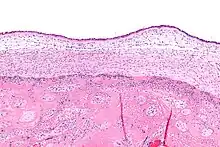

Las infecciones neonatales son infecciones del neonato (recién nacido) adquiridas durante el desarrollo prenatal o en las primeras cuatro semanas de vida (periodo neonatal).[1] Las infecciones neonatales pueden contraerse por transmisión de madre a hijo, en el canal de parto durante el parto, o contraerse después del nacimiento.[2] Algunas infecciones neonatales se manifiestan poco después del parto, mientras que otras pueden desarrollarse en el periodo postnatal. Algunas infecciones neonatales, como el VIH, la hepatitis B y la malaria, no se manifiestan hasta mucho después.

El riesgo de infección es mayor en los recién nacidos prematuros o de bajo peso. El síndrome de dificultad respiratoria infantil suele ser una afección de los neonatos prematuros que puede tener consecuencias negativas a largo plazo; también puede surgir tras una infección. En algunos casos, las enfermedades neonatales del tracto respiratorio pueden aumentar la susceptibilidad a futuras infecciones respiratorias y respuestas inflamatorias relacionadas con enfermedades pulmonares.[3]